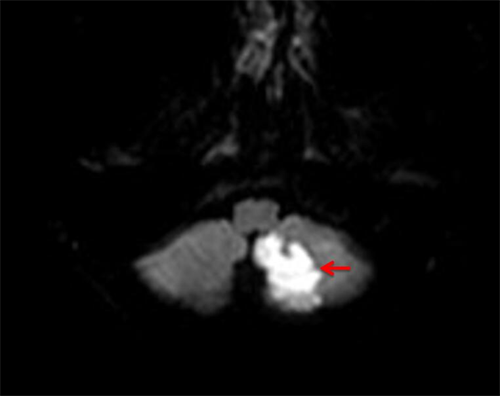

神经内科接诊的刘艳医师仔细询问了病史,发现梁瑶年轻且生活作息规律,脑血管病危险因素很少。但完善头颅磁共振检查后,提示左侧小脑多发急性脑梗死。神经内科副主任、主任医师贺国华迅速组织病例讨论,分析她的发病原因及后期治疗方案。

红色箭头所指“白色”区域为急性梗死病灶